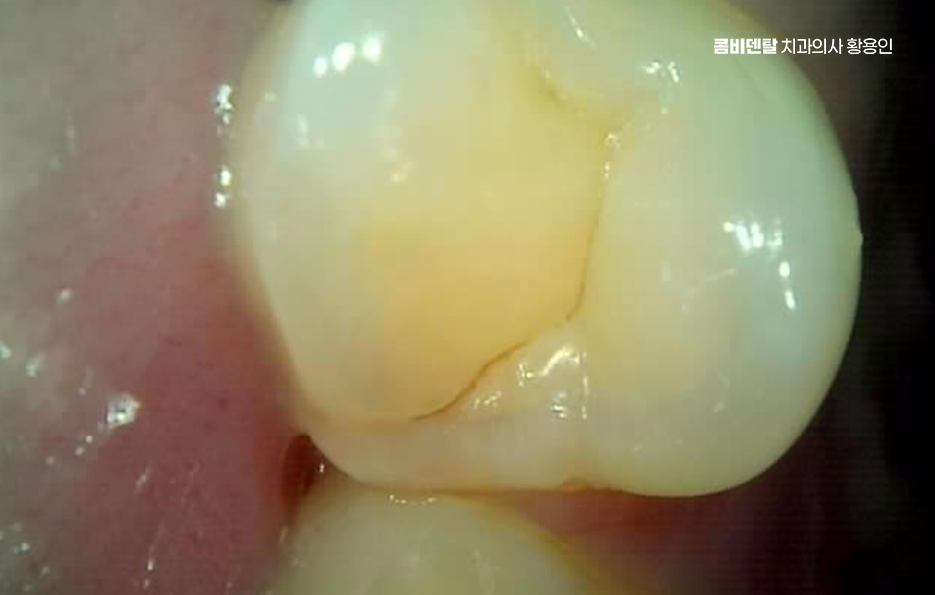

어금니 충치 단계 초기 단계는 법랑질에만 충치가 생긴 상태로 겉으로 보기에는 작은 갈색 점이나 하얀 반점처럼 보일 수 있는데 이 단계에서는 통증이 거의 없으며 차가운 음식이나 단 음식을 먹어도 특별한 느낌이 없을 수 있었어요.

그래서 많은 분들이 그냥 지나치기 쉽지만 이 시점이 가장 치료가 간단한 시기로 충치 부위를 최소한으로 제거하고 레진 같은 재료로 메우면 비교적 간단히 끝날 수 있으며 경우에 따라서는 불소 도포나 관리 개선으로 진행을 늦출 수도 있었어요.